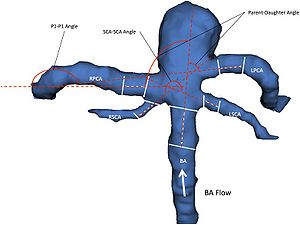

Association Between Vascular Anatomy and Posterior Communicating Artery Aneurysms

|

Publication: World Neurosurg. 2015 Nov;84(5):1251-5. PMID: 26074436 Authors: Can A, Ho AL, Emmer BJ, Dammers R, Dirven CM, Du R. Institution: Department of Neurosurgery, Brigham and Women's Hospital, Harvard Medical School, Boston, MA, USA. Background/Purpose: Hemodynamic stress, conditioned by the geometry and morphology of the vessel trees, plays an important role in the formation of intracranial aneurysms. The aim of this study was to identify image-based location-specific morphologic parameters that are associated with posterior communicating artery (PCoA) aneurysms. Methods: Morphologic parameters obtained from computed tomography angiography of 56 patients with PCoA aneurysms and 23 control patients were evaluated with 3D Slicer, an open-source image analysis software, to generate 3-dimensional models of the aneurysms and surrounding vasculature. Segment lengths, diameters, and vessel-to-vessel angles were examined. To control for genetic and clinical risk factors, the unaffected contralateral side of patients with unilateral PCoA aneurysms was used as a control group for internal carotid artery (ICA)-related parameters. A separate control group with visible PCoAs and aneurysms elsewhere was used as a control group for PCoA-related parameters. Results: Internal carotid artery-related parameters were not statistically different between the PCoA aneurysm and control groups. Univariate and multivariate subgroup analysis for patients with visualized PCoAs demonstrated that a larger PCoA diameter was significantly associated with the presence of a PCoA aneurysm (odds ratio = 12.1, 95% confidence interval = 1.3-17.1, P = 0.04) after adjusting for other morphologic parameters. Conclusions: Larger PCoA diameters are associated with the presence of PCoA aneurysms. These parameters may provide objective metrics to assess aneurysm formation and growth risk stratification in high-risk patients. |

- 4.35 Morphological Parameters Associated with Ruptured Posterior Communicating Aneurysms

- 3.29 Morphology Parameters for Mirror Posterior Communicating Artery Aneurysm Rupture Risk Assessment